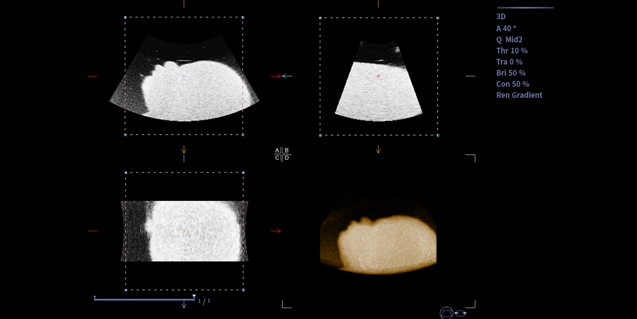

容积探头V6-2

腹部,胎儿检查

临床图像